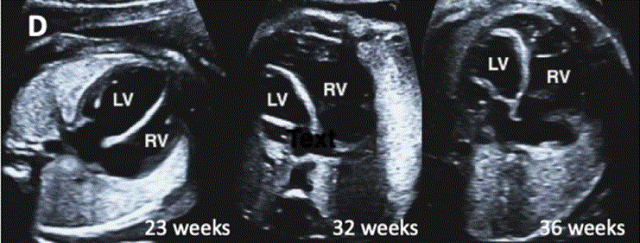

图27进展性主动脉狭窄。一例23周胎儿的严重主动脉狭窄,伴有扩张和低动力性左心室(LV)伴心内膜弹性纤维变性。(A) 彩色多普勒显示,主动脉瓣(箭头)开始出现花彩血流(左),频谱多普勒显示阶差为 25 毫米汞柱(右(B) 二尖瓣(MV)流入是单相的,持续时间短(左),二尖瓣反流提示左心室收缩压高(46毫米汞柱压力梯度加左心房压力;右图)。(C)存在逆行主动脉弓流(红色,左)和左至右心房流(红色、右)是预测由于通过左心的流量减少而在妊娠期间发展的进行性左心发育不全的额外发现。(D)LV逐渐变为球状,长度缩短,到36周时不再形成心尖。